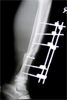

Wound debridement with minimal fixation and external fixator

Pre

Op